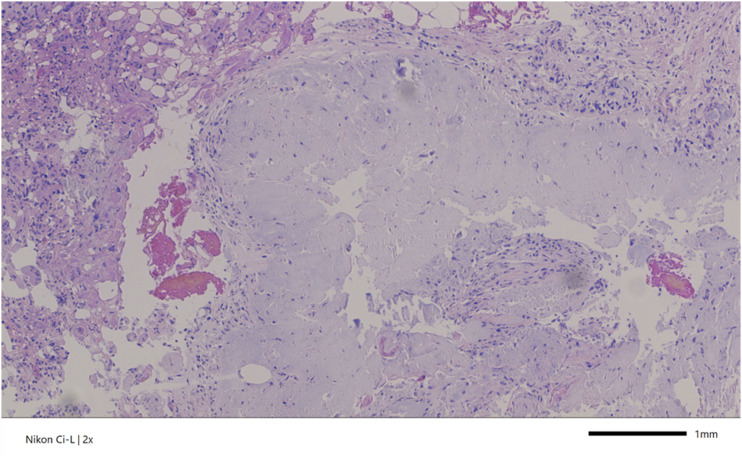

Case description: A 79-year-old woman with a 3-year history of low back pain presented with severe left-sided pain and mobility impairment. Initial examination showed lumbar tenderness and normal muscle strength. Computed tomography (CT) and magnetic resonance imaging scans revealed a calcified extradural mass occupying the anterior portion of the lumbar spinal canal, most likely associated with the posterior longitudinal ligament. The patient underwent L3-L5 hemilaminectomies and dorsal spondylodesis, removing a whitish intraspinal mass. Histopathology confirmed CPPD. Post-surgery, the patient experienced initial pain relief but required emergency surgery due to complications. Over the next year, her mobility and pain improved significantly.

Discussion: Spinal CPPD manifests with varied clinical presentations, complicating diagnosis. Imaging reveals calcifications ranging from deposits to mass-like lesions causing compression. CT provides detailed visualization of characteristic calcifications, aiding in diagnosis, while histopathology remains the gold standard. Multidisciplinary collaboration is vital for accurate diagnosis and optimal management.